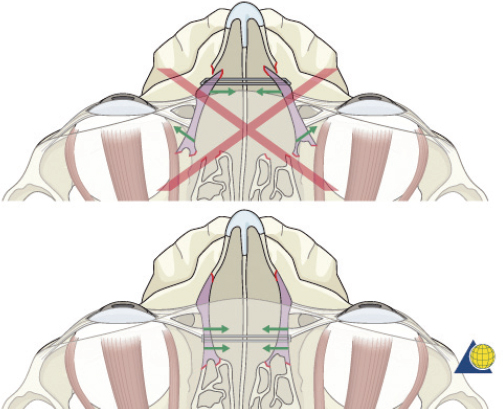

Type II fractures require more extensive surgical exposure, and generally need two- or three-point fixation. A subperiosteal dissection is used to locate, but not avulse, the medial canthal tendon. If the comminution is mild and the central fragment can be plated, the injury is treated as a type I fracture. If the central fragment is too small to be plated, transnasal wires should be used. Transnasal wires are generally easiest to place prior to any osteosynthesis of the surrounding fractures. Initially holes are drilled in the central fragment above and below the medial canthal tendon ( Fig. 63.62 ). Both ends of a 28-gauge wire (or a wire suture) are passed from lateral to medial, leaving the free ends on the medial surface of the central fragment ( Fig. 63.63 ). Once the central fragment is controlled with the wire, a drill may be used to define a transnasal path for passage of the wire ( Fig. 63.64 ). The drill must be passed posterior and superior to the lacrimal fossa, and below the frontoethmoid suture line (to avoid intracranial injury). A 14-gauge spinal needle (or angiocatheter with outer sheath removed) is then passed through the drill hole. The needle is passed in a retrograde fashion, through the ethmoid complex, from the uninjured to the injured side. A malleable retractor is placed medial to the globe on the injured side to provide protection as the spinal needle is passed. The wires are then passed transnasally through the lumen of the needle, and the needle is removed ( Fig. 63.65 ). The wire is then tightened while the central fragment is medialized with external pressure, securing the wire on a miniscrew in the frontal bone ( Fig. 63.66 ). It is critical that tension is maintained on the wire throughout fixation. Any laxity in the wire may allow the medial canthal tendon to lateralize with concomitant loss of fracture reduction. It is difficult, if not impossible, to overcorrect the reduction. Appropriate wire placement posterior and superior to the lacrimal fossa will pull the canthus medially without rotation. Transnasal wires placed anterior to the lacrimal fossa will result in lateral rotation of the central fragment and iatrogenic telecanthus ( Fig. 63.67 ).25

The cantilever technique involves adaption of a miniplate to run across the inferior aspect of the frontal bone and into the medial, anterior orbit in such a way that the deepest hole corresponds to the location that a transnasal wire would be passed (e.g., posterosuperior to the lacrimal fossa) ( Fig. 63.65 ). Before the plate is fixated, the wire suture attached to the avulsed medial canthal tendon is passed through the deepest hole of the plate ( Fig. 63.70 ). The wire is then passed transnasally, via a spinal needle, to the contralateral orbit ( Fig. 63.71 ). Disruption of the medial orbit often alleviates any need for drilling. A malleable retractor should be used to protect the globe while passing the spinal needle across the skull base. Screws are then placed into the frontal bone to align the distal hole of the miniplate in the correct 3D position for the canthal ligament reconstruction ( Fig. 63.72 ). Finally tension is placed on the wire while external pressure is applied to assist with medialization of the injured canthus. The final location of the canthal repair is confirmed and the transnasal wire is anchored to a screw placed on the contralateral frontal bone ( Fig. 63.73 ). An alternative technique for repair of the medial canthal tendon is the use of a canthal barb ( Fig. 63.74 ). The canthal barb is passed through a small cutaneous incision and through the medial canthal ligament, anchoring the barb within the ligament ( Figs. 63.75 and 63.76 ). The wire is then passed transnasally as described above and anchored on the contralateral frontal bone. Alternatively, the canthal barb can be placed through the miniplate and anchored on the ipsilateral. This has the advantage of avoiding transnasal wire placement, however sliding the wire through the plate becomes much more challenging due to the acute angle of placement.